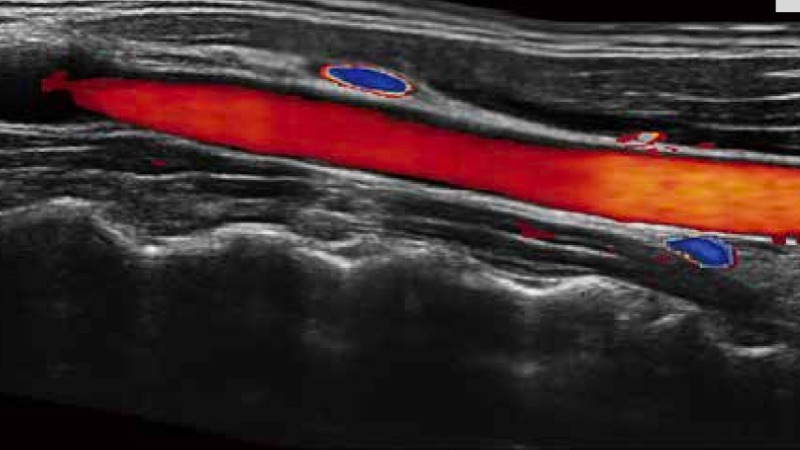

開立醫(yī)療通過不斷的技術(shù)創(chuàng)新,為大眾的生命健康提供持續(xù)關(guān)愛。P12 Plus采用全新一代超聲成像平臺,新平臺旨在將真實(shí)還原組織解剖結(jié)構(gòu)作為首要目標(biāo)。平臺采用全新集成化硬件模塊,搭載新一代芯片,系統(tǒng)性能得到大幅提升,為您的診斷提供了豐富的臨床信息。優(yōu)異的圖像表現(xiàn),豐富的探頭配置,全面的應(yīng)用功能,為您日常診斷提供了可靠的助手。

彩色多普勒超聲診斷系統(tǒng)